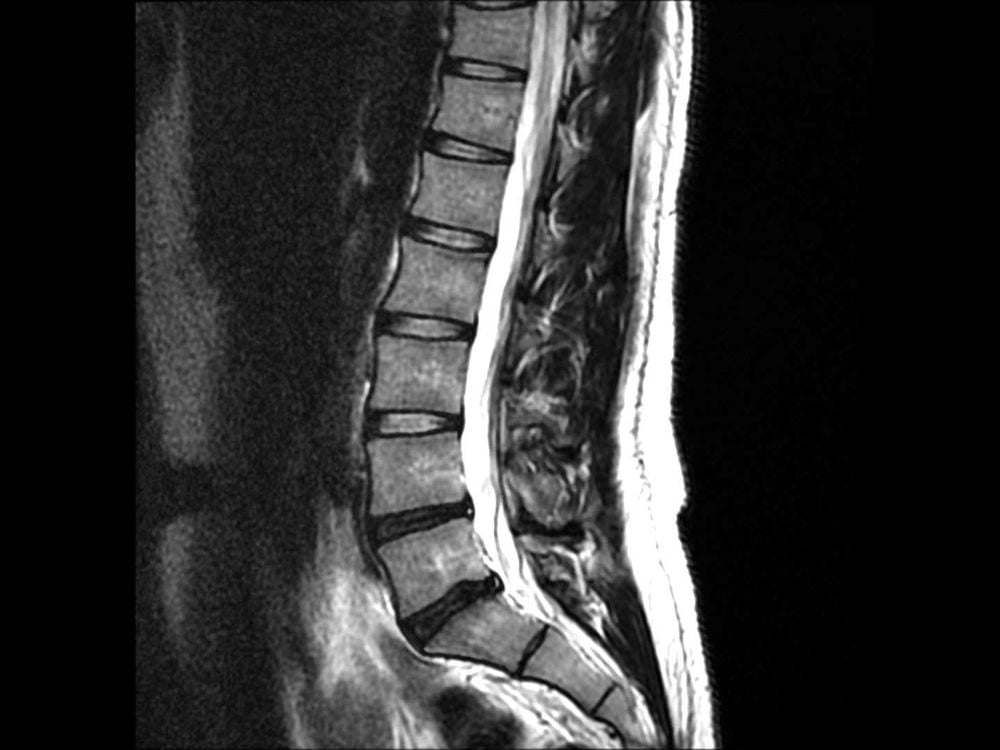

Thoát vị đĩa đệm thắt lưng là tình trạng thoát vị xảy ra ở vùng cột sống thắt lưng (L1–L5), đặc biệt phổ biến tại L4–L5 và L5–S1.

Cảm giác này có thể là đau buốt, nóng rát hoặc như điện giật. Đây là dấu hiệu điển hình của thoát vị đĩa đệm tại các tầng L4–L5 hoặc L5–S1 và là lý do nhiều người tìm kiếm cụm từ “đau lưng lan xuống chân có phải thoát vị đĩa đệm không”.

Việc chẩn đoán thoát vị đĩa đệm không chỉ dựa vào hình ảnh MRI mà cần kết hợp giữa triệu chứng lâm sàng và đánh giá chuyên môn để tránh điều trị quá mức hoặc sai hướng.